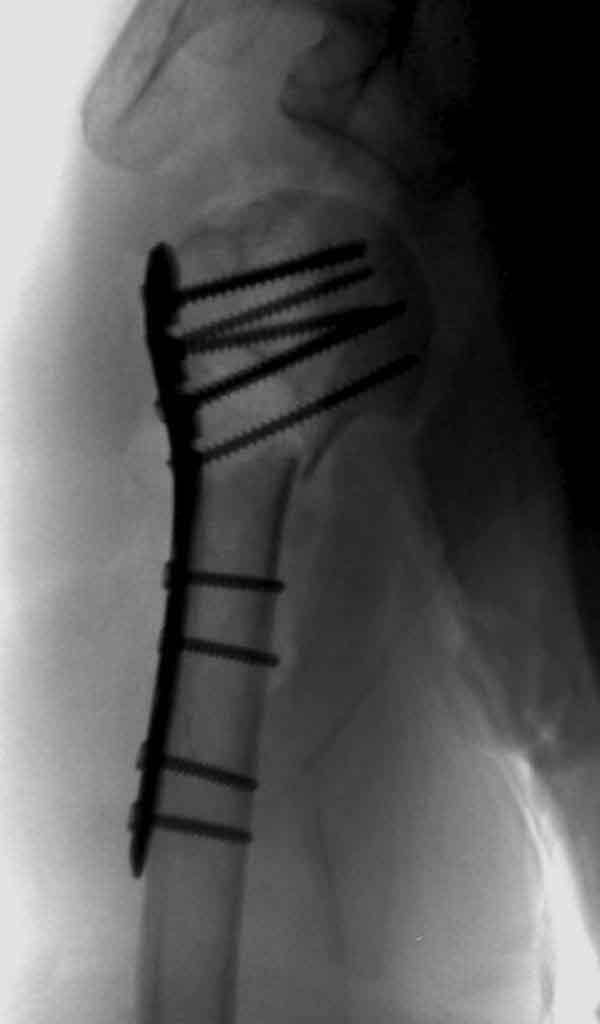

Уважаемы коллеги! Прошу помочь определиться с тактикой лечения пациентки. В феврале в отделение поступила пациентка с оскольчатым переломо-вывихом головки плечевой кости. Выполнена операция -остеосинтез блокируемой пластиной. Костная пластика не производилась. На контрольных рентгенограммах остается сублюксация головки и смещение большого бугорка. Интраоперационно бугорок подшивался с помощью лавсановых нитей. Послеоперационно: ношение косыночной повязки и пассивные движения в плечевом суставе в течение 2,5-х месяцев без особенностей. Через 2,5 месяца при попытке выполнения пассивно-активных движений произошел передний вывих плечевой кости.Вся реабилитация производилась по месту жительства. Таким образом существование вывиха в течение 1 месяца. Боли не беспокоят. Нейрососудистых нарушений в конечности нет. Что вы можете посоветовать: пластику, эндопротез, артродез? Заранее спасибо.

мне кажется ,что на послеоперационном снимке, также имеется сублюксация головки.сколько годов пациентке?

Уважаемый коллега. На мой взгляд имеющаяся дислокация головки обусловлена на мой взгляд имеющейся у пациента обширной травмой ротаторного аппарата. В пользу данной точки зрения могу привести следующее: на представленных Вами рентгенограммах хорошо заметен отрыв большого бугорка со смещением отломков который как известно является точкой прикрепления коротких наружных ротаторов плеча. Последующая миграция данного фрагмента и неполноценная репозиция его при первичном остеосинтезе с нестабильной фиксацией на мой взгляд и обусловили создавшуюся ситуацию. то что пациента не беспокоят боли позволю подвергнуть сомнению поскольку сам занимаюсь хирургией плеча и с подобными ситуациями сталкивался неоднократно. На мой взгляд в настоящее время целесообразно проведение повторного оперативного вмешательства с адекватным восстановлением ротаторного аппарата, поскольку дальнейшее затягивание сложившейся ситуации уменьшает шанс на успех данного вмешательства.

Для адекватного лечения необходимо знать состояние костного компонента - нужно КТ с артрографией что поможет частично оценить состояние сухожилий и лабриум. Уже по снимку можно сказать что существует большой костный дефект в задне-наружном сегменте.